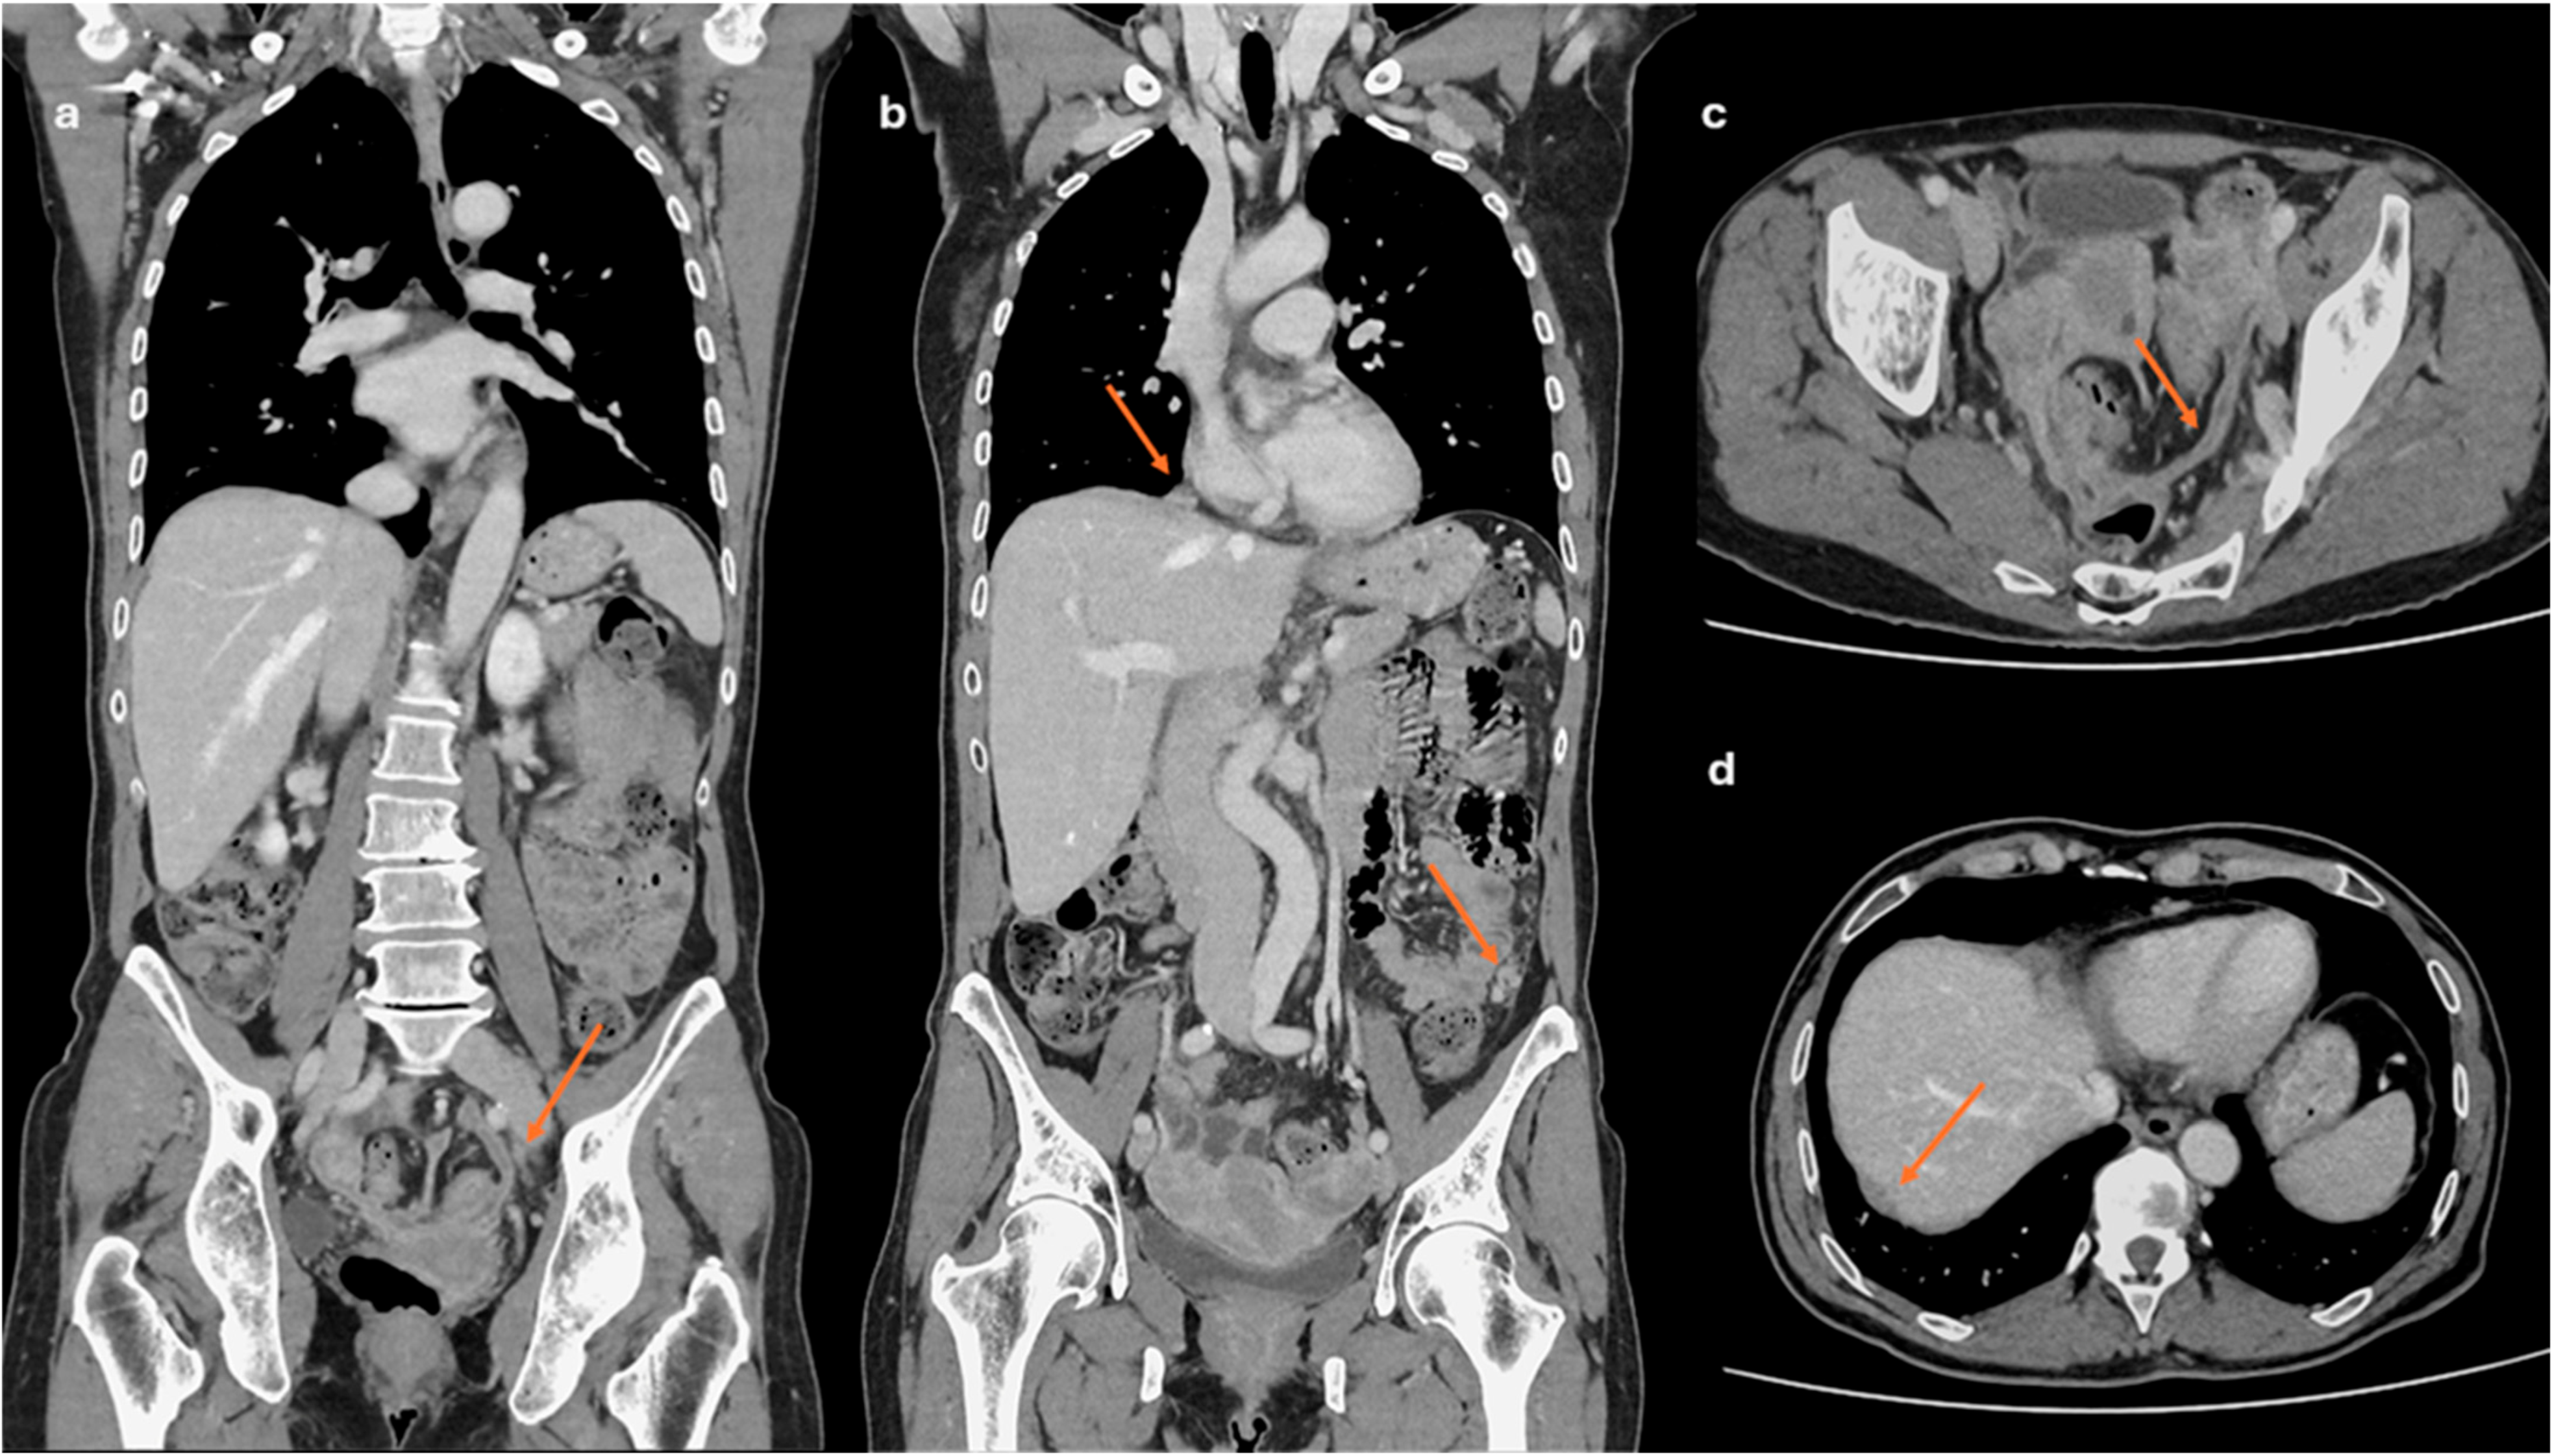

2.2. CT Imaging

- Lesions associated with the presence of peritoneal implants and/or secondary disease localization (Figure 6)

- Chiu, S.; Tsitsiou, Y.; Da Silva, A.; Qin, C.; Fotopoulou, C.; Rockall, A. CT and MRI in Advanced Ovarian Cancer: Advances in Imaging Techniques. Korean J. Radiol. 2025, 26, 841. [Google Scholar] [CrossRef] [PubMed]

- Rizzo, S.; Avesani, G.; Panico, C.; Manganaro, L.; Gui, B.; Lakhman, Y.; Andrieu, P.C.; Bharwani, N.; Rockall, A.; Thomassin-Naggara, I.; et al. Ovarian cancer staging and follow-up: Updated guidelines from the European Society of Urogenital Radiology female pelvic imaging working group. Eur. Radiol. 2025, 35, 4029–4039. [Google Scholar] [CrossRef]

- Avesani, G.; Arshad, M.; Lu, H.; Fotopoulou, C.; Cannone, F.; Melotti, R.; Aboagye, E.; Rockall, A. Radiological assessment of Peritoneal Cancer Index on preoperative CT in ovarian cancer is related to surgical outcome and survival. Radiol. Med. 2020, 125, 770–776. [Google Scholar] [CrossRef] [PubMed]